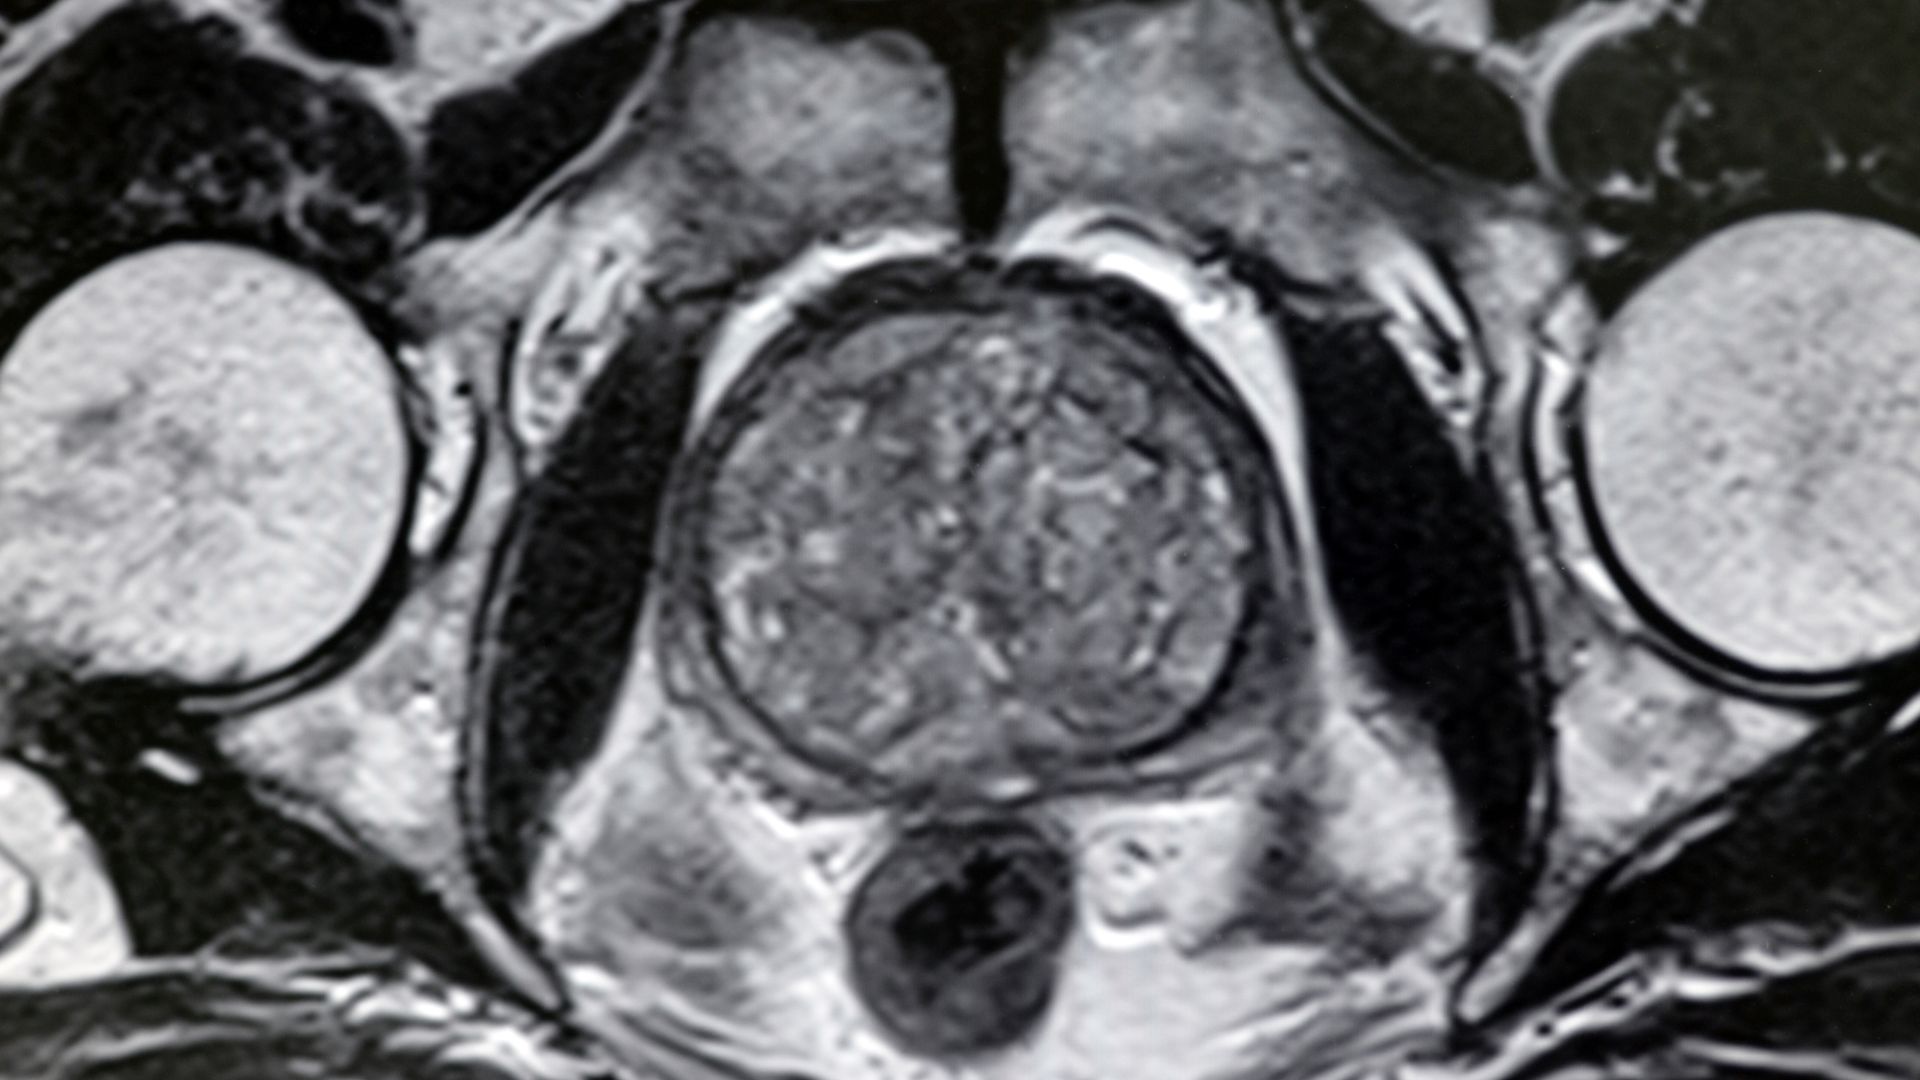

При съмнение за рак се прави мултипараметричен ядрено-магнитен резонанс (ЯМР). Новите резонанси прецизно хващат туморните процеси, до 5-6 милиметра. PSA-density представлява разделянето на PSA, спрямо обема на простатната жлеза. Когато съотношението е под една единица, има по-малка плътност.